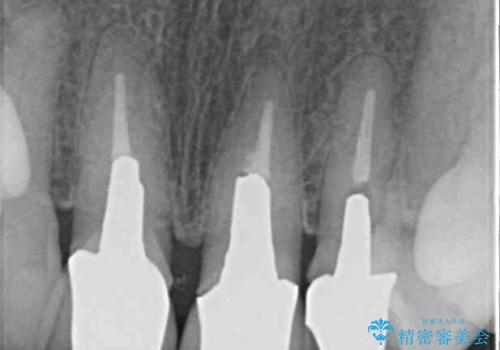

- 黄色みのある前歯のセラミックを、明るい色に替えたいとのことで来院された患者様です。

透明感がないことも気になっていたため、オールセラミッククラウンでは透けてしまう可能性のある金属の土台をファイバーコアに置き換え、1トーン明るいクラウンにて仕上げていくこととしました。